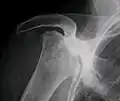

X-ray images of avascular necrosis in the early stages usually appear normal. In later stages it appears relatively more radio-opaque due to the nearby living bone becoming resorbed secondary to reactive hyperemia.[2] The necrotic bone itself does not show increased radiographic opacity, as dead bone cannot undergo bone resorption which is carried out by living osteoclasts.[2] Late radiographic signs also include a radiolucency area following the collapse of subchondral bone (crescent sign) and ringed regions of radiodensity resulting from saponification and calcification of marrow fat following medullary infarcts.

Radiography of total avascular necrosis of right humeral head. Woman of 81 years with diabetes of long evolution.